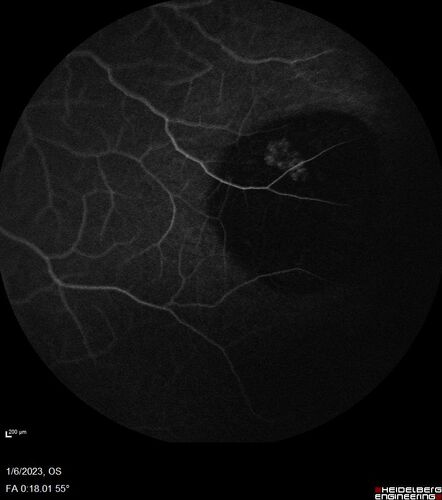

32 year old female with normal vision and CHRPE

CHRPE - with FA